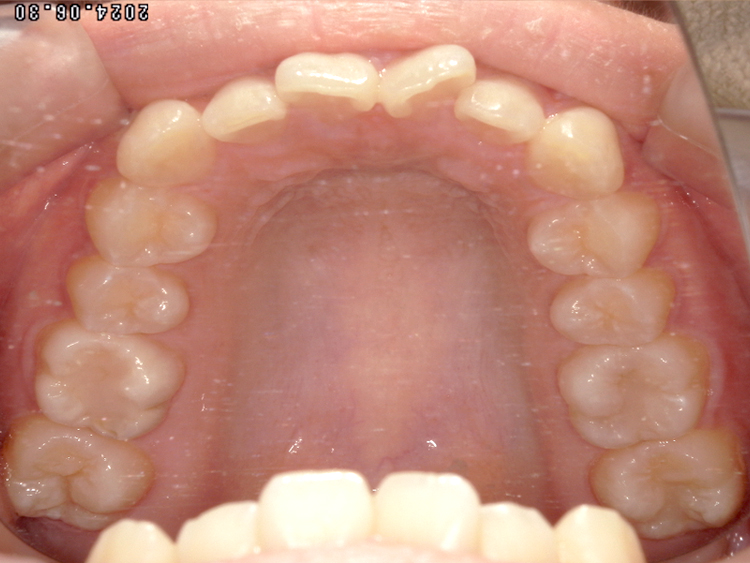

症例4

Before

After

| 主訴 | 上下前歯のがたつき |

|---|---|

| 年齢 | --- |

| 治療 期間 |

約9ヶ月 |

| 治療 内容 |

インビザラインiGoで上下顎の治療。 |

| 治療費 | ¥550,000(税込)/調整料含む |

| 治療のリスク | 矯正終了後は、リテーナーを指示通りに使用し、歯の後戻りを防ぐ必要があります。 |